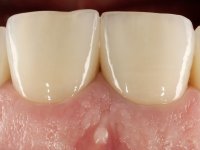

Foi proposto ao paciente fazer uma reabilitação total com infraestruturas em zircónia revestidas a cerâmica. No maxilar superior, seriam realizadas 6 coroas (1.3/1.2/1.1/2.1/2.2/2.3), uma ponte de 3 elementos (1.4/1.5/1.6) e uma ponte de 4 elementos (2.4/2.5/2.6 e 2.7). No maxilar inferior, foram propostas 7 coroas (4.3/4.2/4.1/3.1/3.2/3.5 /3.6) e duas pontes (4.4//4.5/4.6) e (3.3/3.4#/3.4).O objetivo seria subir a D.V.O., descruzar a mordida do lado direito, eliminar as infiltrações e as exposições radiculares e reabilitar o paciente com estruturas protéticas com aspeto mais natural.

A primeira acção terapêutica foi tentar melhorar o tratamento endodôntico dos dentes (2.4/2.5/4.2)). A sua manutenção em boca seria condicionada pelo sucesso desta intervenção. Seguidamente foram feitas impressões em alginato e registo inter-maxilar em silicone para confeção em laboratório de uma ponte provisória em acrílico com reforço. O objetivo desta ponte provisória seria ensaiar o aumento da D.V.O. e descruzar a mordida do lado direito. Foi utilizado um monobloco de 13 dentes com o dente 2.6 com o pôntico. As coroas e as pontes foram removidas e os remanescentes coronários foram repreparados. A ponte provisória foi rebasada primeiramente com acrílico auto-polimerizável e de seguida com resina composta. Após 2 semanas de permanência em boca, foram feitas as impressões para confeção da ponte provisória inferior também realizada em laboratório. Especial cuidado foi colocado na remoção das coroas antigas, sendo feito primeiramente um corte axial que permitiu que fossem removidas de uma forma menos traumática. A temporização foi feita durante 8 semanas, permitindo que os tecidos gengivais estabilizassem posicionalmente. As impressões definitivas foram realizadas após afastamento gengival utilizando a técnica do fio único impregnado. Foi utilizada a técnica de dupla mistura com dupla viscosidade (putty soft e light).Simultaneamente foi realizada a recolha das relações inter-maxilares e o registo com arco facial. Foram confecçionados os modelos de trabalho e feita a sua correta montagem em articulador semi-ajustável. Em seguida foram feitas infra estruturas em zircónia que posteriormente foram revestidas por cerâmica. A prova de “biscoito” foi realizada em boca para avaliação estética e funcional sendo também avaliado o seu assentamento e ajuste. A reabilitação definitiva foi cimentada em boca utilizando um cimento de ionómero de vidro reforçado por resina.